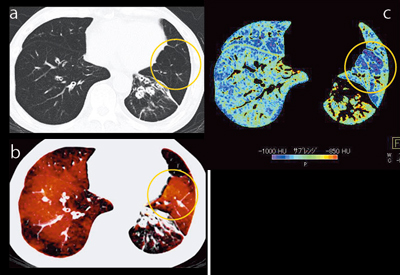

一方,下肺野(図3)では,単純CTとparenchyma画像でLAAが認められる部分に,Xeが取り込まれている(○)。この理由は不明であり,air trappingの可能性もあるが,こういったケースの存在をXeイメージで知ることができる。

図3 症例1:肺気腫,GOLDU(下肺野)

a:単純CT b:Xeイメージ c:parenchyma画像